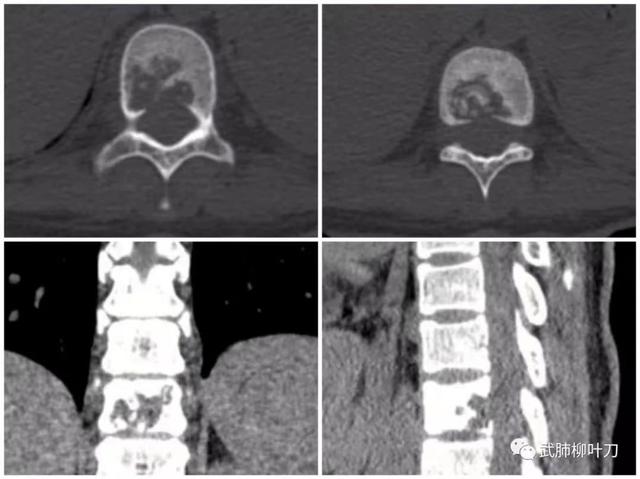

医生给她进行了检查发现,小史感染了结核杆菌。一开始,结核杆菌主要攻击肺部,但小史年轻,除偶尔咳嗽外,并无太多不适,所以并未让她察觉结核杆菌的存在。之后,结核杆菌随血流播散到脊椎。钻入椎管的病菌发现此处环境适合,就“安家落户”,大肆繁殖,并“啃噬”第十、第十一节胸椎,还形成脓肿,挤压椎管内的脊髓。

根据检查结果,武汉市肺科医院外科主任戴希勇带领团队,迅速对小史进行了手术治疗。他们打开椎管,清理病菌及其造成的脓肿。并取小史自体骨骼,对受侵蚀的脊椎骨进行修补、加固。